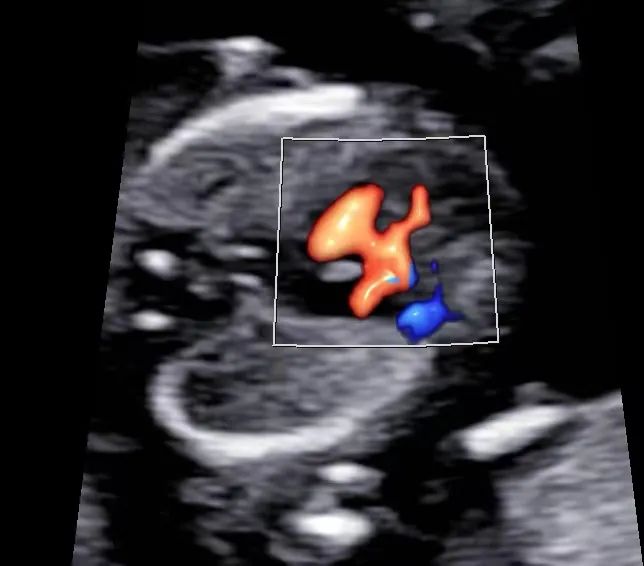

近日,一位准妈妈,27岁,2022年曾接受霍奇金淋巴瘤治疗,目前怀孕14周,来到我院超声科进行早孕期胎儿结构筛查。此次检查中,胎儿的颈项透明层(NT)厚度为1.7mm,处于正常范围。然而,超声检查发现胎儿心脏存在室间隔膜周部缺损,对此情况建议孕妇前往产前诊断门诊进行咨询。这是我院超声科首次成功完成的早孕期胎儿结构筛查,同时也是池州市首例此类检查。

随着超声诊断仪器性能的不断提高以及超声医师诊断经验的日益丰富,早孕期胎儿检查的深度和细致程度也在不断提高。在早孕期,我们不仅可以筛查与胎儿非整倍体染色体异常相关的软指标,还可以对胎儿的解剖结构进行检查,从而提前发现某些胎儿结构畸形,实现早期诊断和早期处理。